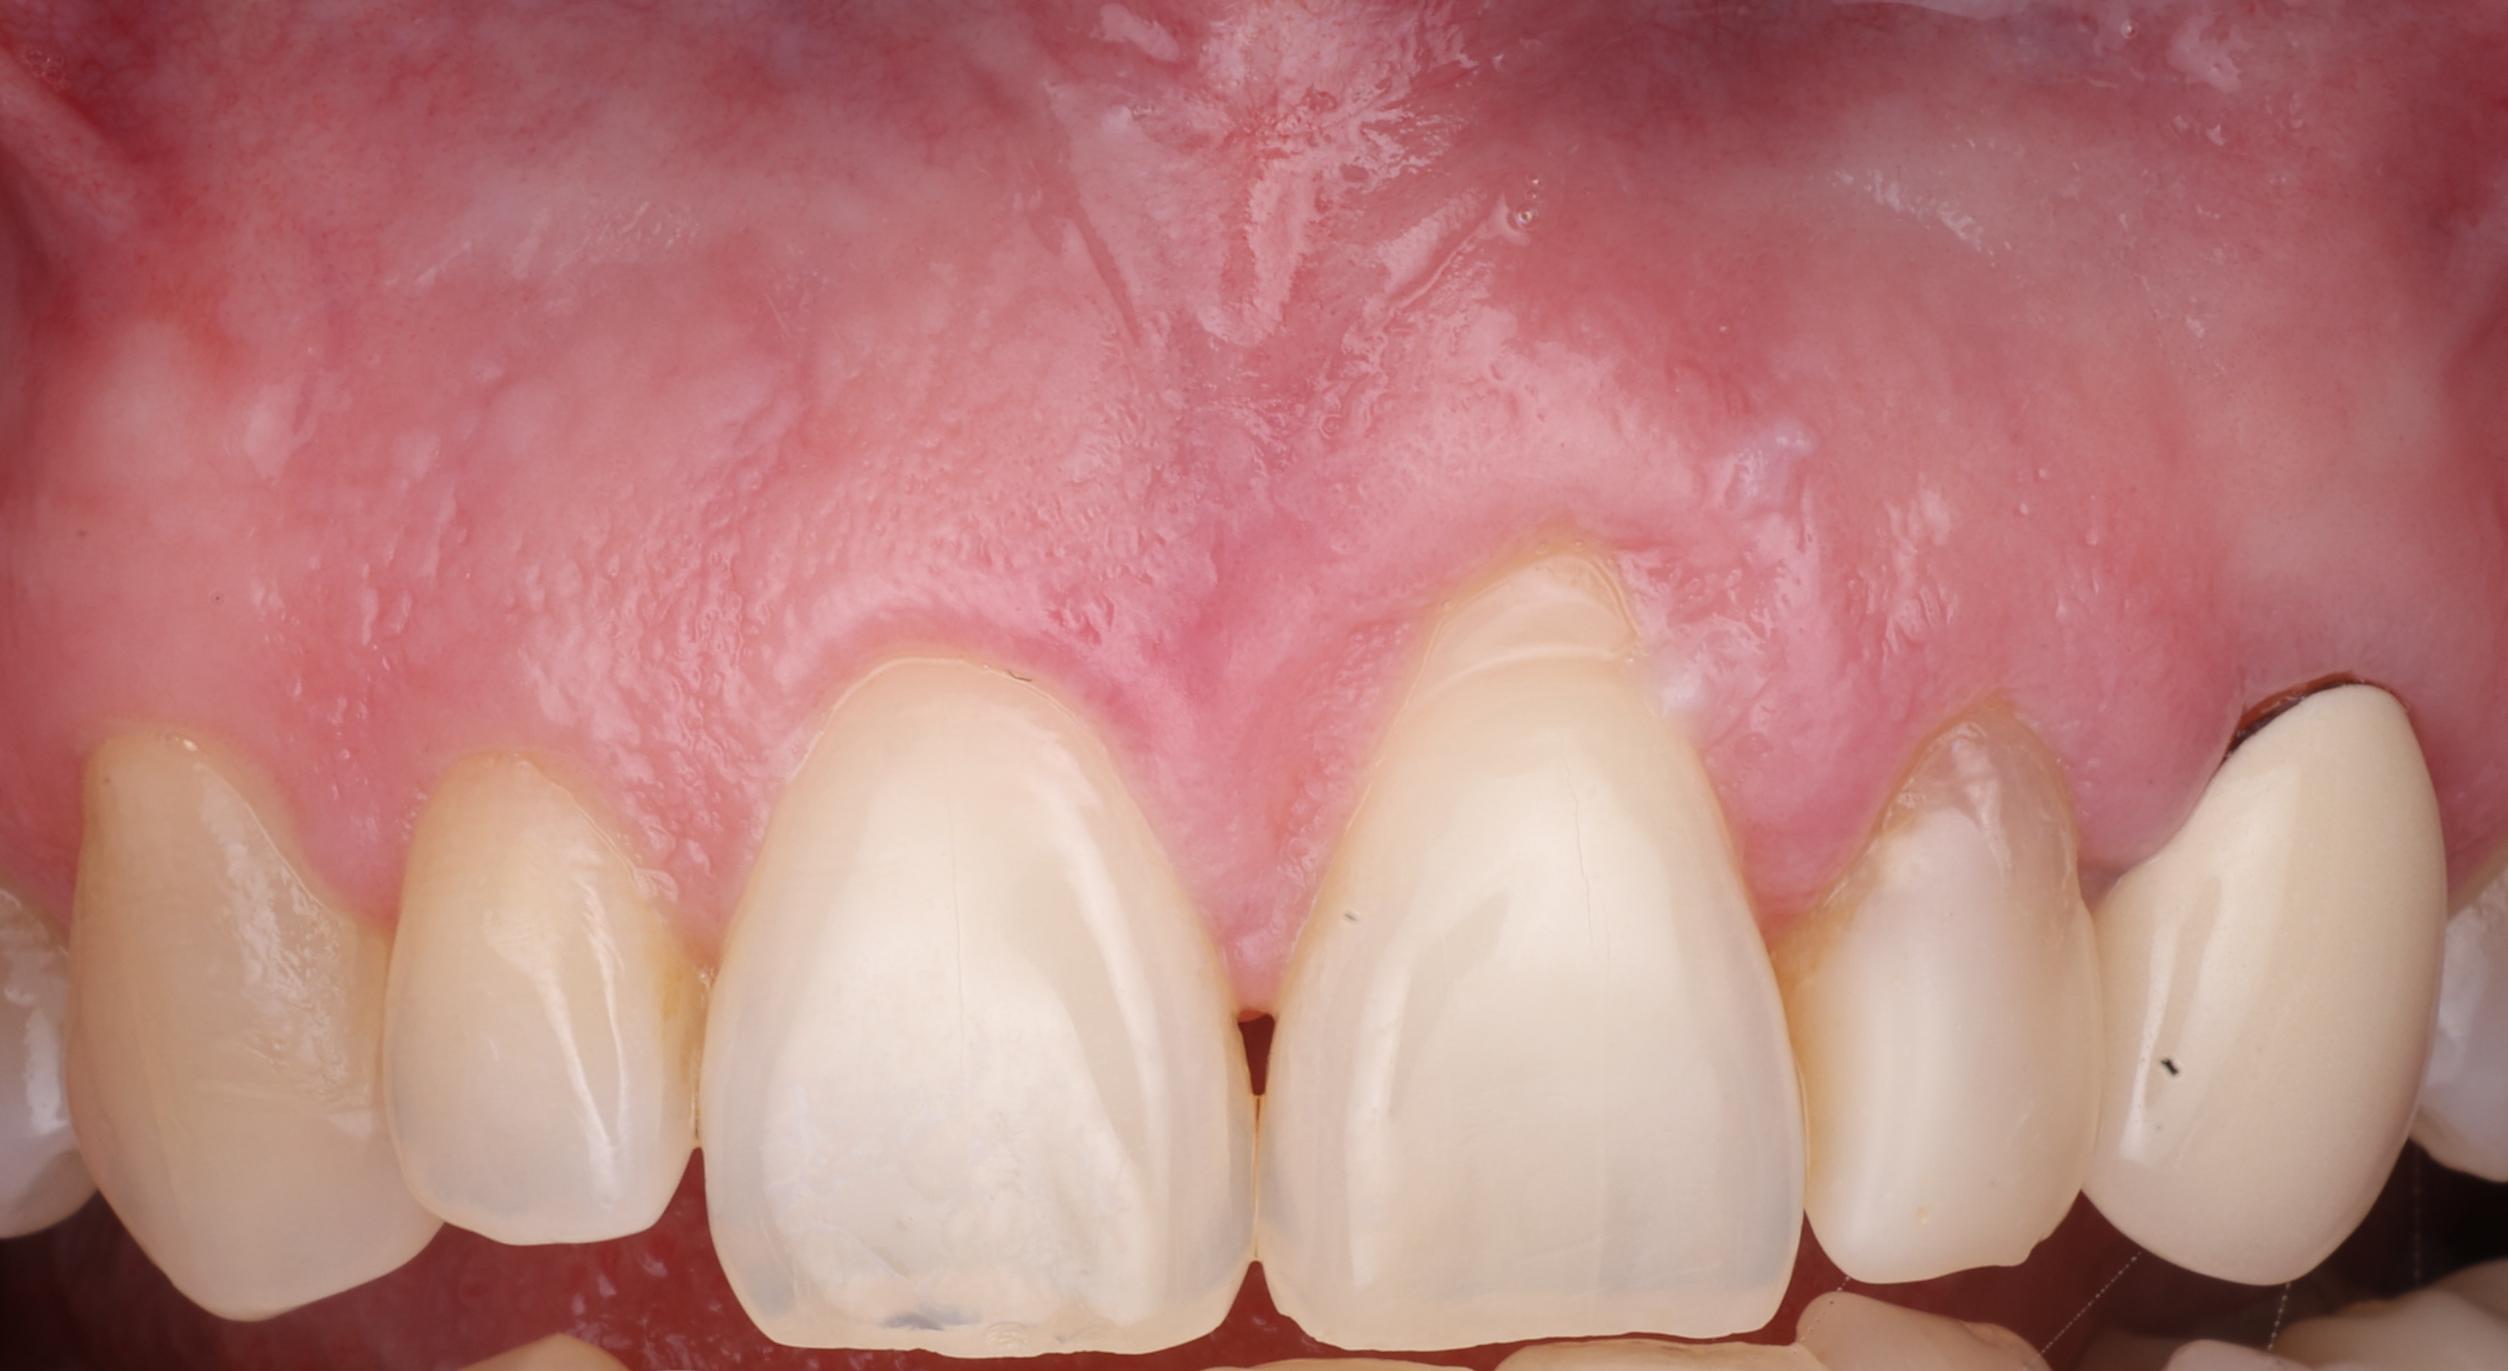

Gum Recession Treatment

Before After

Before Image

After Image